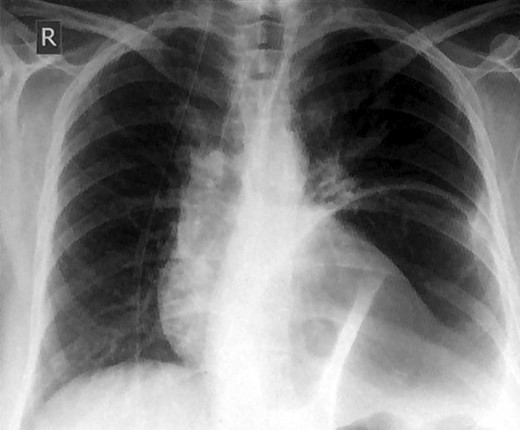

A 49-year-old woman presented to our emergency department with a 2-week history of epigastric pain and vomiting with no prior trauma. Her past medical history included hypertension, iron deficiency anemia, laparoscopic cholecystectomy and an open uterine myomectomy. Upon arrival to the emergency department, she had a pulse of 135 beats per minute, a blood pressure of 110/90 mmHg, a respiratory rate of 20/min, a body temperature of 37.6°C and an oxygen saturation of 98% on room air. Her clinical examination revealed tenderness over the epigastric region, and her bowel sounds were hyperactive. She had decreased air entry at the left basal region of the chest. The initial laboratory results were white blood cell count 22.1 × 109/l (neutrophilic), blood urea nitrogen 7.8 mmol/l, creatinine 121 umol/l and normal liver function tests, amylase and lipase. Her lactic acid was 0.9 mmol/l. A chest radiograph demonstrated a significant air-fluid level near the left lung base (Fig. 1).

Chest x-ray showing an elevated air-fluid left in the left basal lung region.